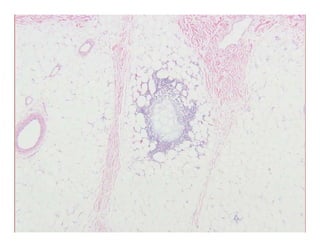

Lupus profundusLupus profundusLupus profundusLupus profundus

Lobular panniculitis with prominent lymphocytic infiltrateLobular panniculitis with prominent lymphocytic infiltrateLobular panniculitis with prominent lymphocytic infiltrateLobular panniculitis with prominent lymphocytic infiltrate

–– Characteristic feature:Characteristic feature: paraseptal lymphoid follicles, sometimes withparaseptal lymphoid follicles, sometimes with

germinal centergerminal center

Uncommon in other panniculitidesUncommon in other panniculitides

Late lesions with dystrophic calcificationLate lesions with dystrophic calcification